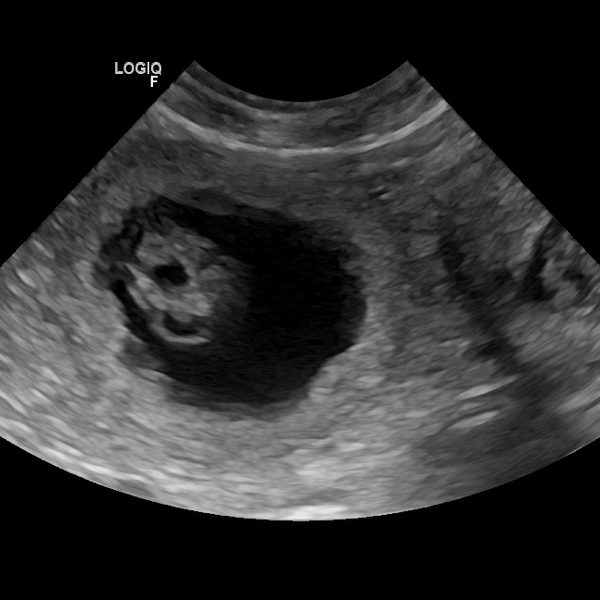

Wir haben Welpen von unserer Weltsiegerin "Jusie" x Multichampion "Blade"